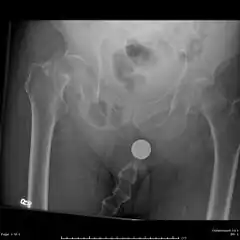

X-ray image of a femoral shaft fracture

Radiography

Bilateral femoral neck fractures

Anterior-posterior (AP) and lateral radiographs are typically obtained.[4]

In order to rule out other injuries, hip, pelvis, and knee radiographs are also obtained.[5]

The hip radiograph is of particular importance, because femoral neck fractures can lead to osteonecrosis of the femoral head.[4]